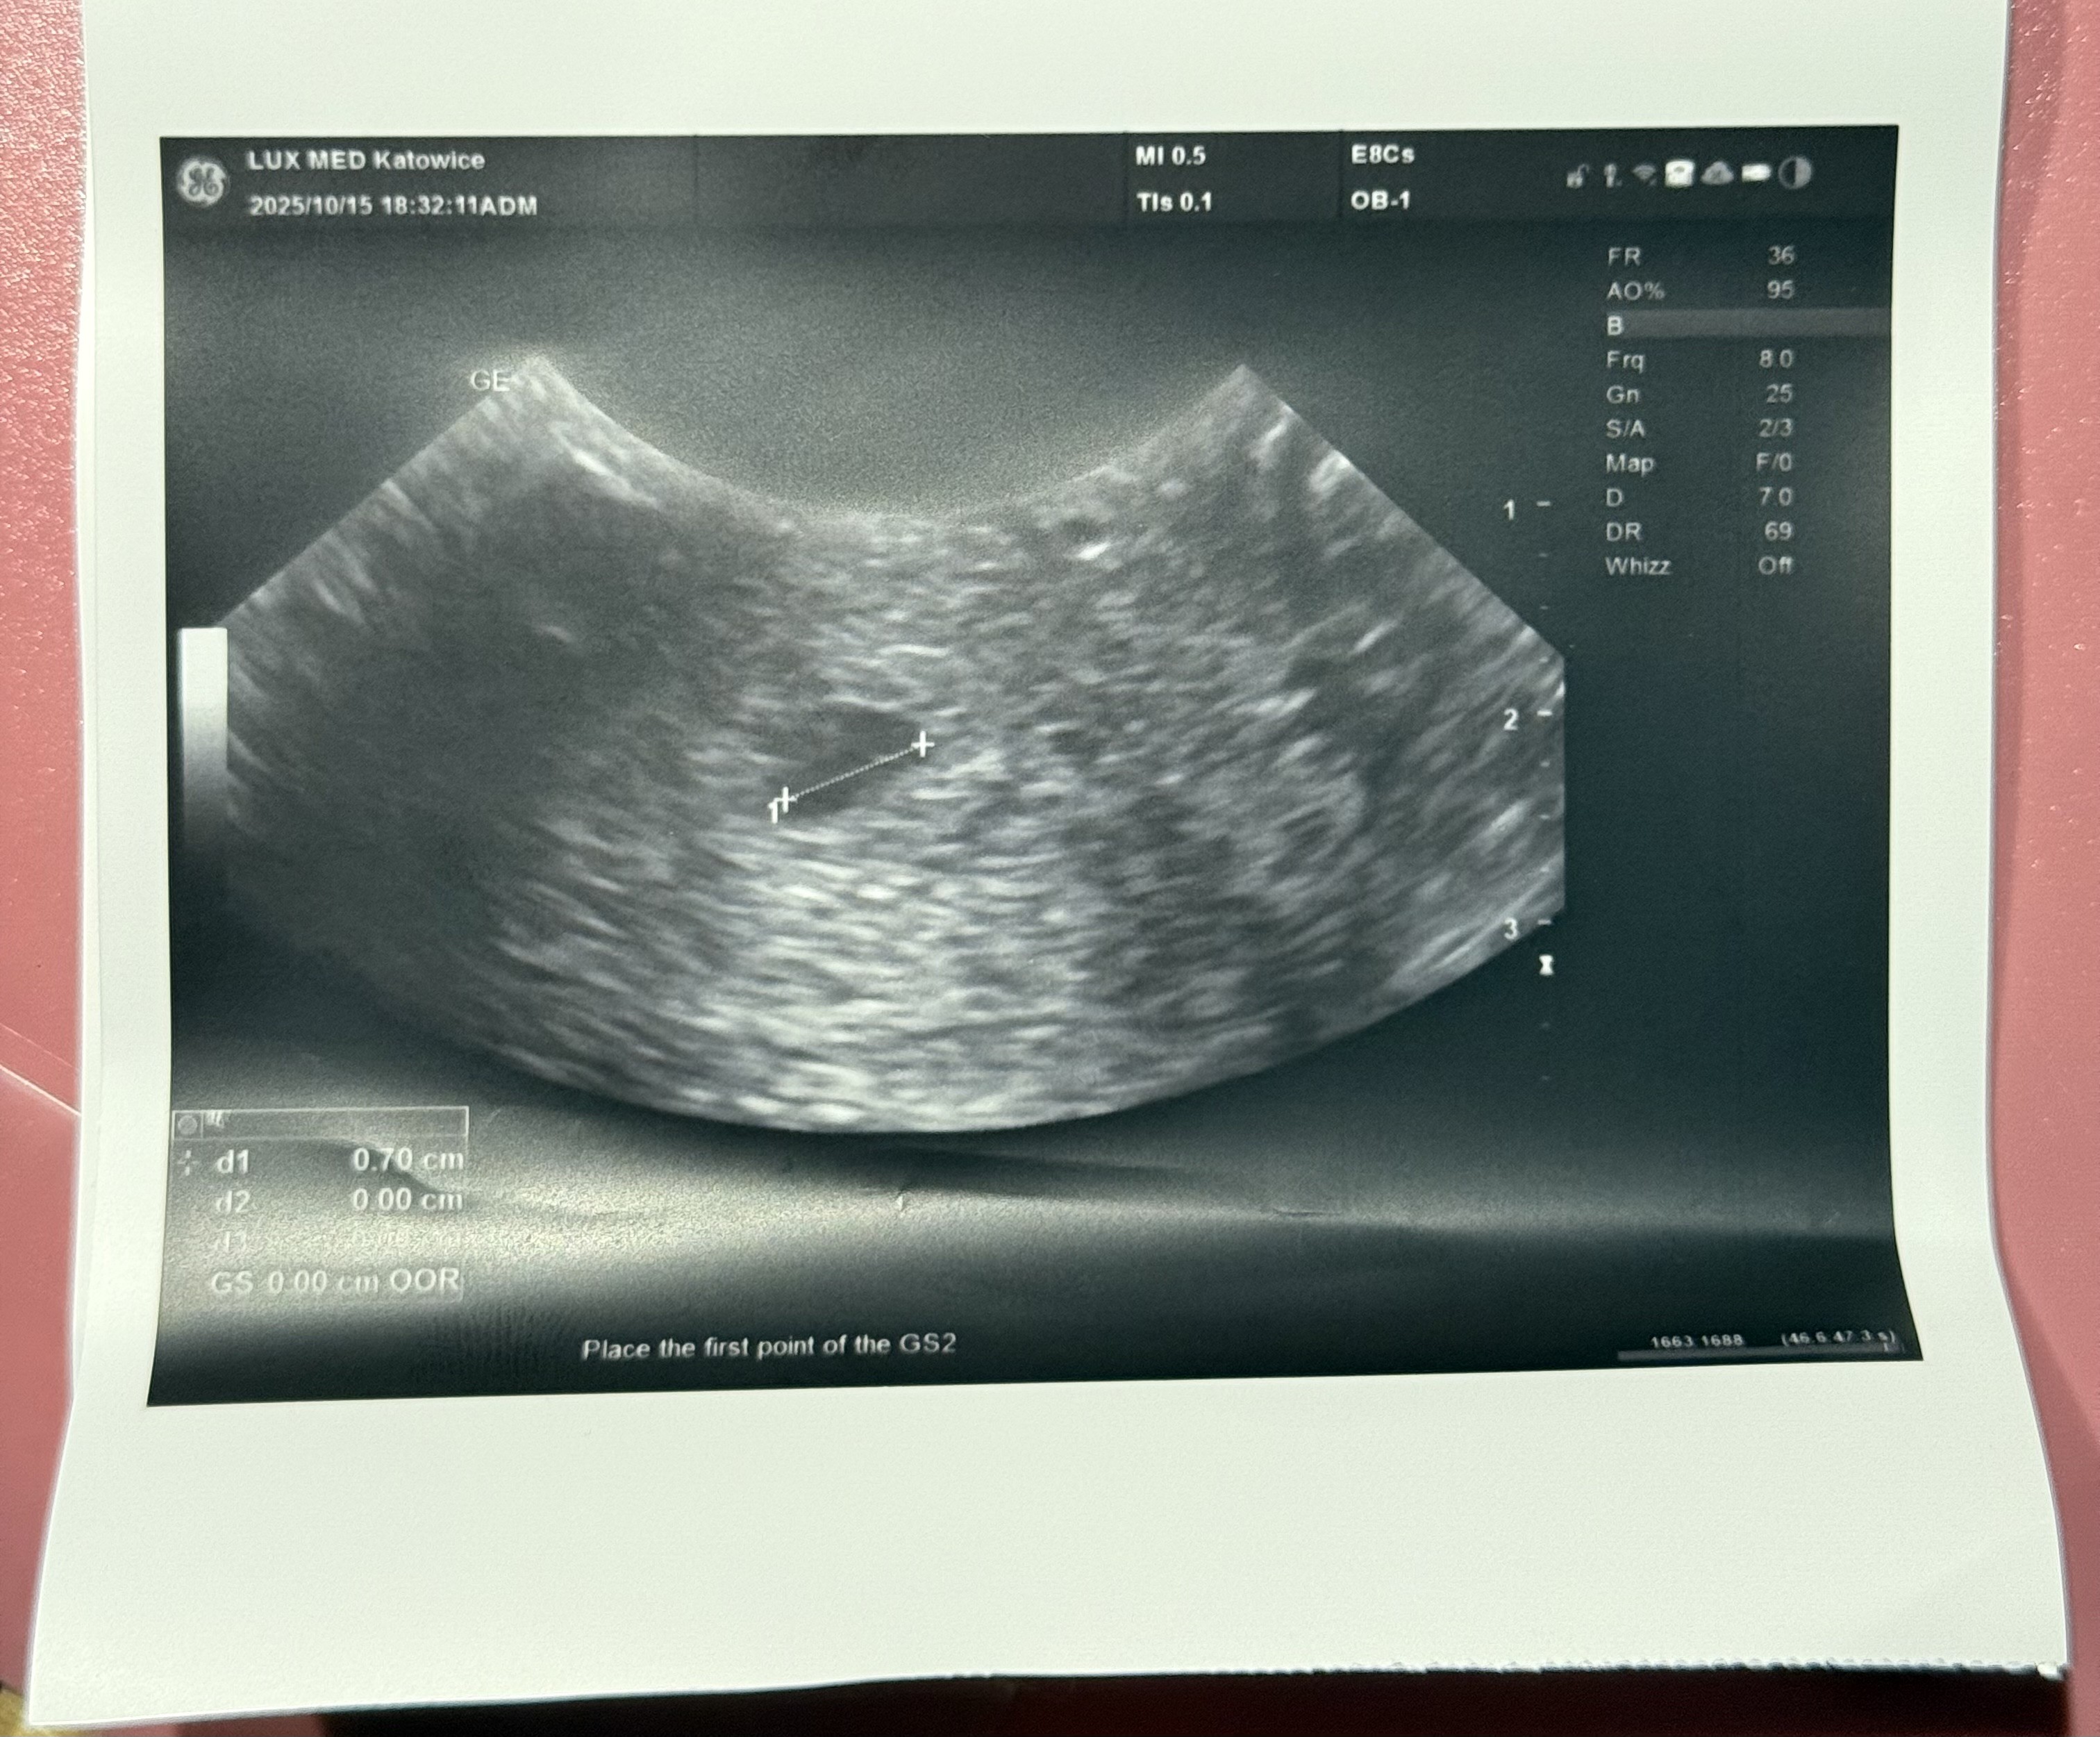

Dziewczyny jestem po wizycie, mamy 7mm pęcherzyk.. Lekarz powiedział, że na ten moment wszystko dobrze wygląda i za tydzień w środę znowu wizyta i USG zobaczymy czy pojawi się zarodek i serduszko..

Mówił, że zaczyna się coś pokazywać powoli no ale tak definitywnie tego jeszcze nie potwierdził, powiedział, że za tydzień będziemy wiedzieć więcej ale uspokajał mnie i mówił, że jego zdaniem wszystko będzie okej, także staram się wierzyć w jego słowaŚwietna wiadomośćmówił lekarz czy jest cialko żółte czy tylko pęcherzyk?